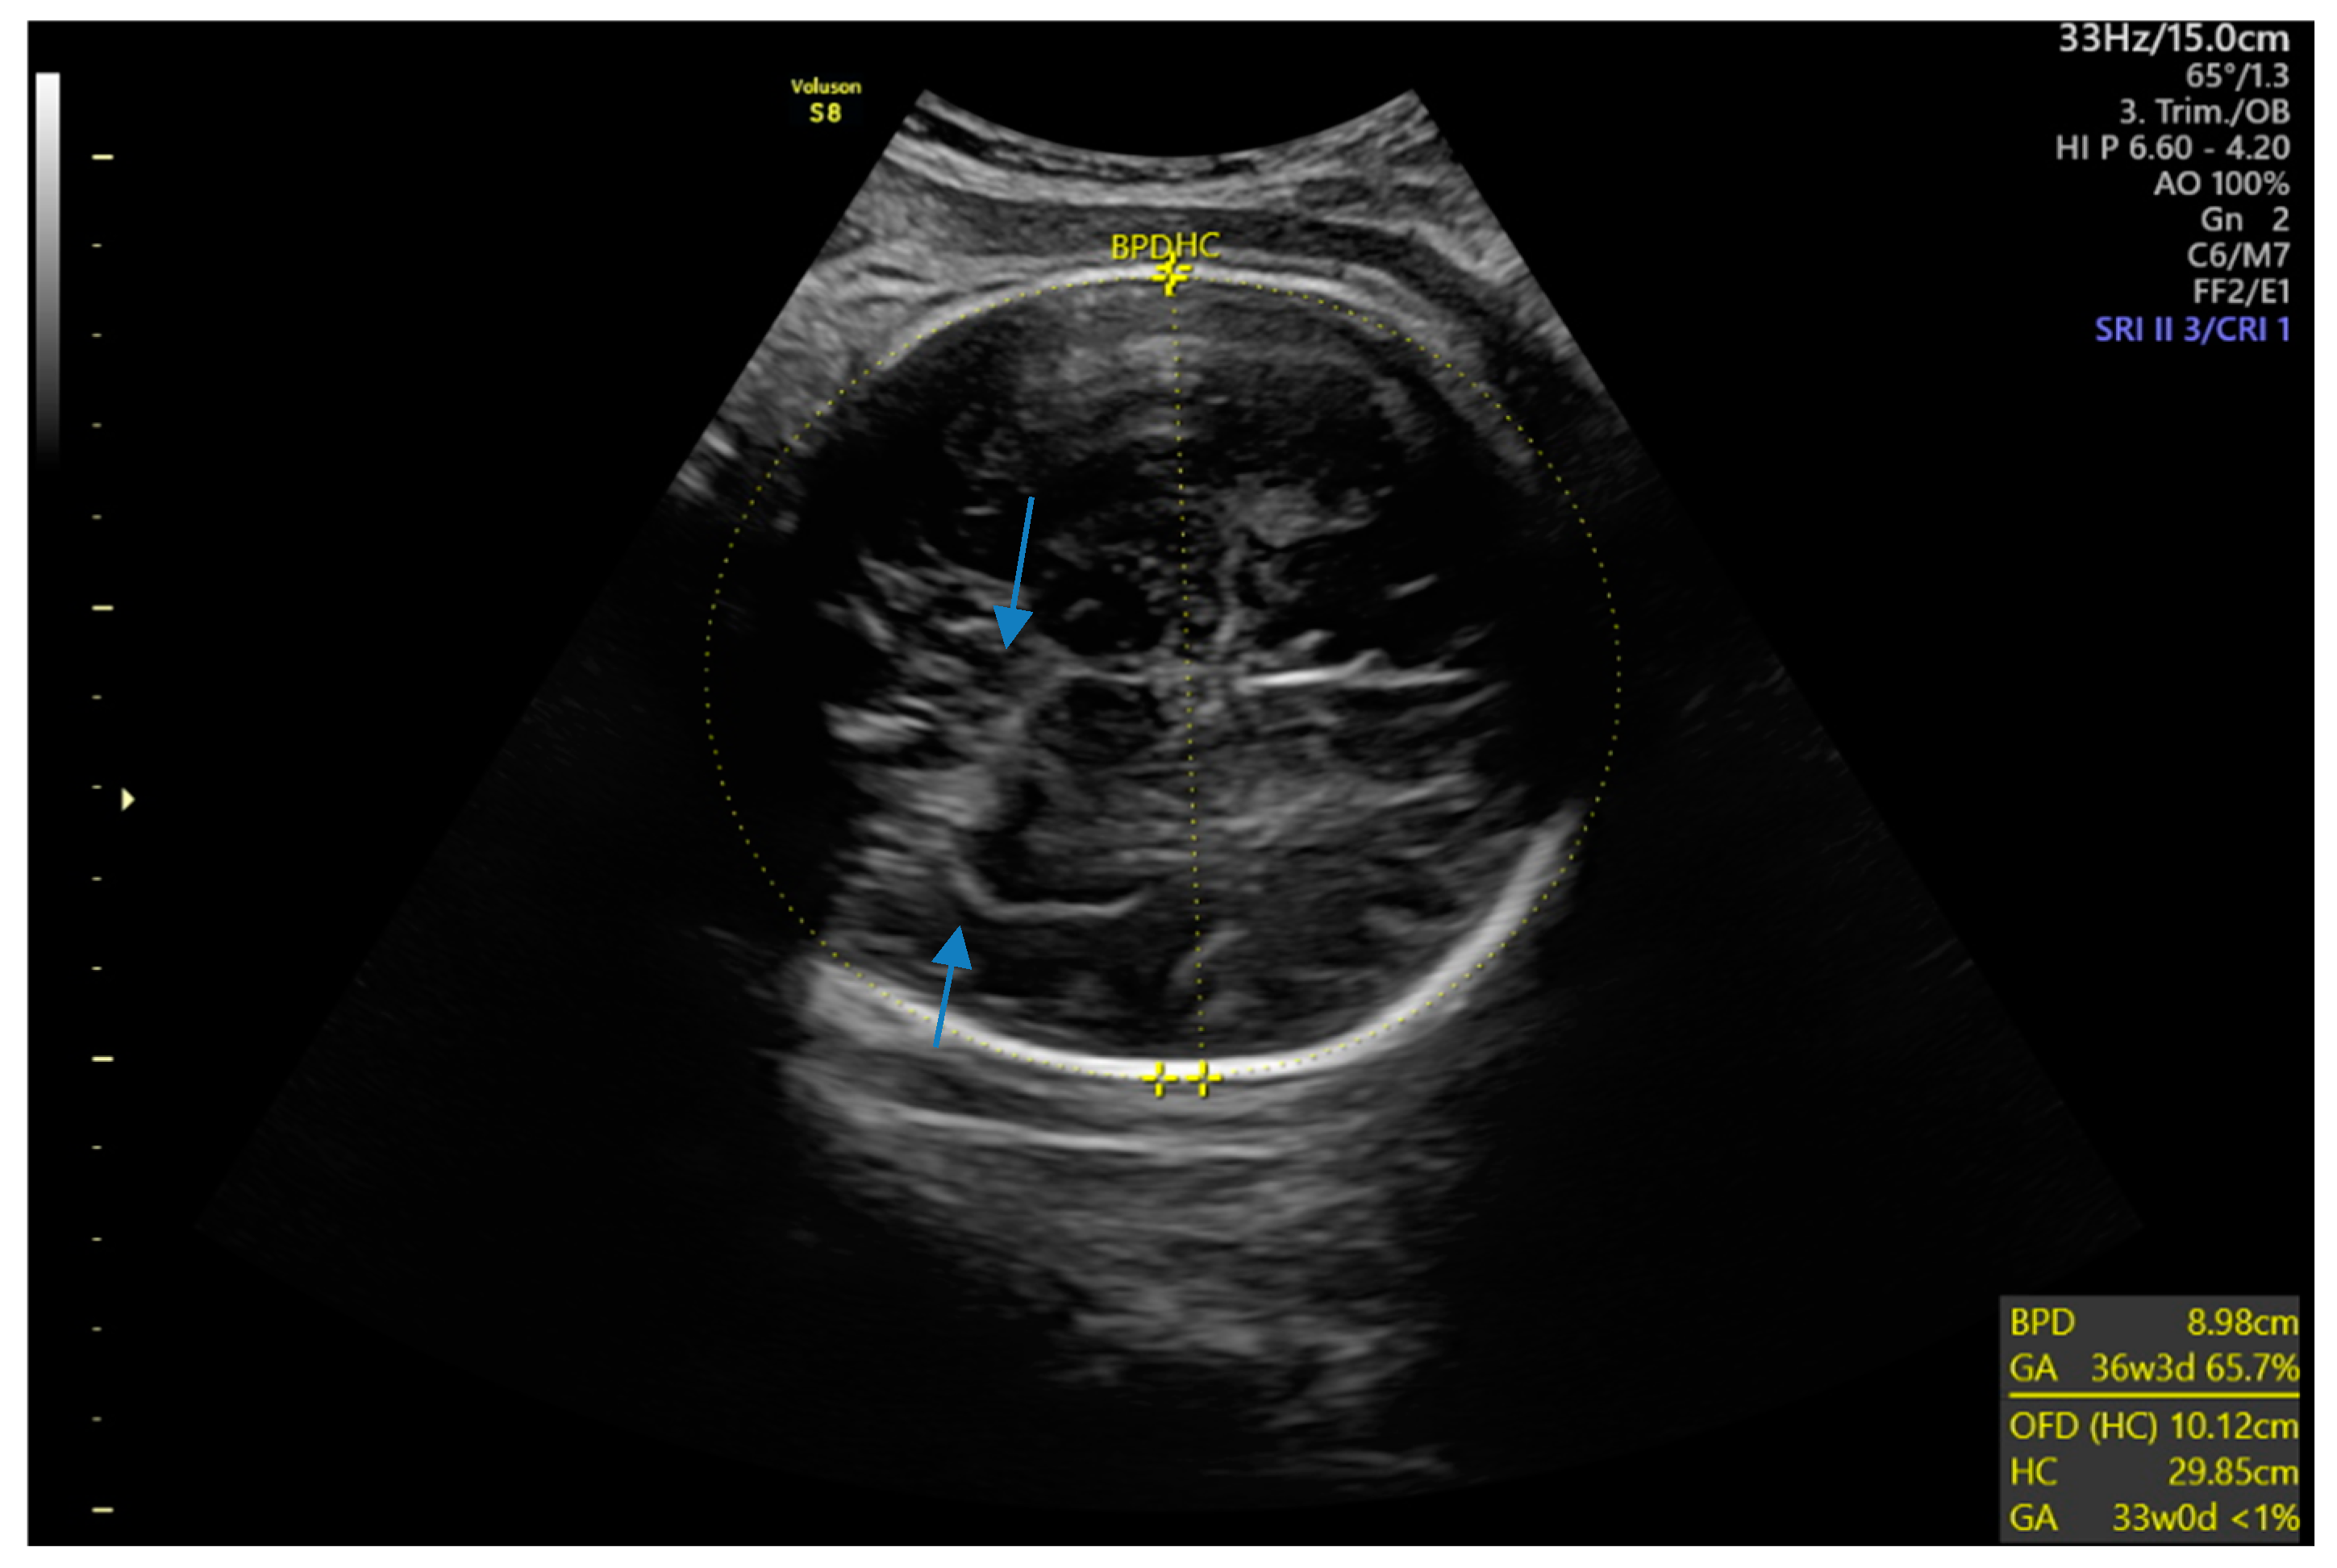

Six months later, a second ultrasound scan and a consecutive MRI scan to follow-up and control the success of the therapy were performed. The ultrasound revealed a decrease in the size of the cyst from 10 cm in maximal diameter to 9 cm and showed multiple circular septations, indicating an involuting cyst (Figure 7). In contrast to the preceding MRI scan, typical T2 hypointense membrane-like structures were observed within the lesion in T2WI. These represented most probably the floating membranes, the typical water-lily sign (Figure 8). T1WI (Figure 9) showed the cyst as a hypointense lesion, but the membranes could only be clearly observed in T2WI. Consecutively, the cyst was classified as WHO-CE3A.

Figure 7.

Second ultrasound scan: The right lobe of the liver reveals a round, fluid-filled cystic lesion with several septations (arrows), indicating the degenerating cystic wall of a stage-CE3a hydatid cyst.